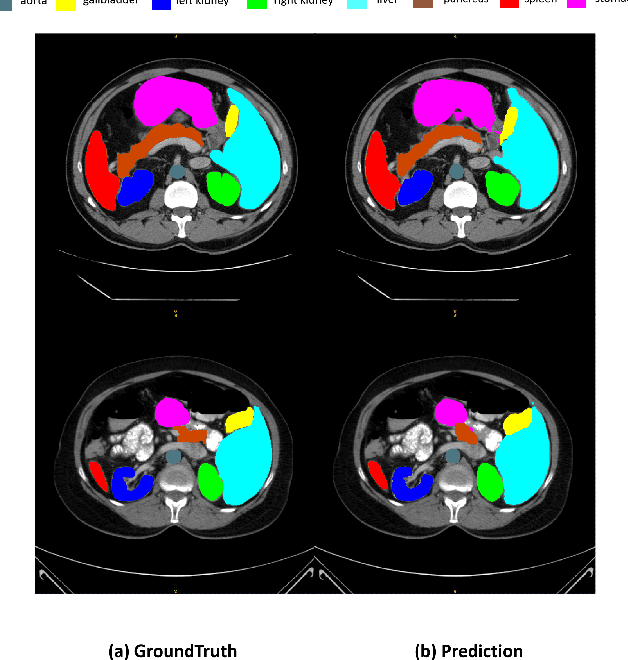

Abstract:Recently, foundation models have been introduced demonstrating various tasks in the field of computer vision. These models such as Segment Anything Model (SAM) are generalized models trained using huge datasets. Currently, ongoing research focuses on exploring the effective utilization of these generalized models for specific domains, such as medical imaging. However, in medical imaging, the lack of training samples due to privacy concerns and other factors presents a major challenge for applying these generalized models to medical image segmentation task. To address this issue, the effective fine tuning of these models is crucial to ensure their optimal utilization. In this study, we propose to combine a complementary Convolutional Neural Network (CNN) along with the standard SAM network for medical image segmentation. To reduce the burden of fine tuning large foundation model and implement cost-efficient trainnig scheme, we focus only on fine-tuning the additional CNN network and SAM decoder part. This strategy significantly reduces trainnig time and achieves competitive results on publicly available dataset. The code is available at https://github.com/11yxk/SAM-LST.